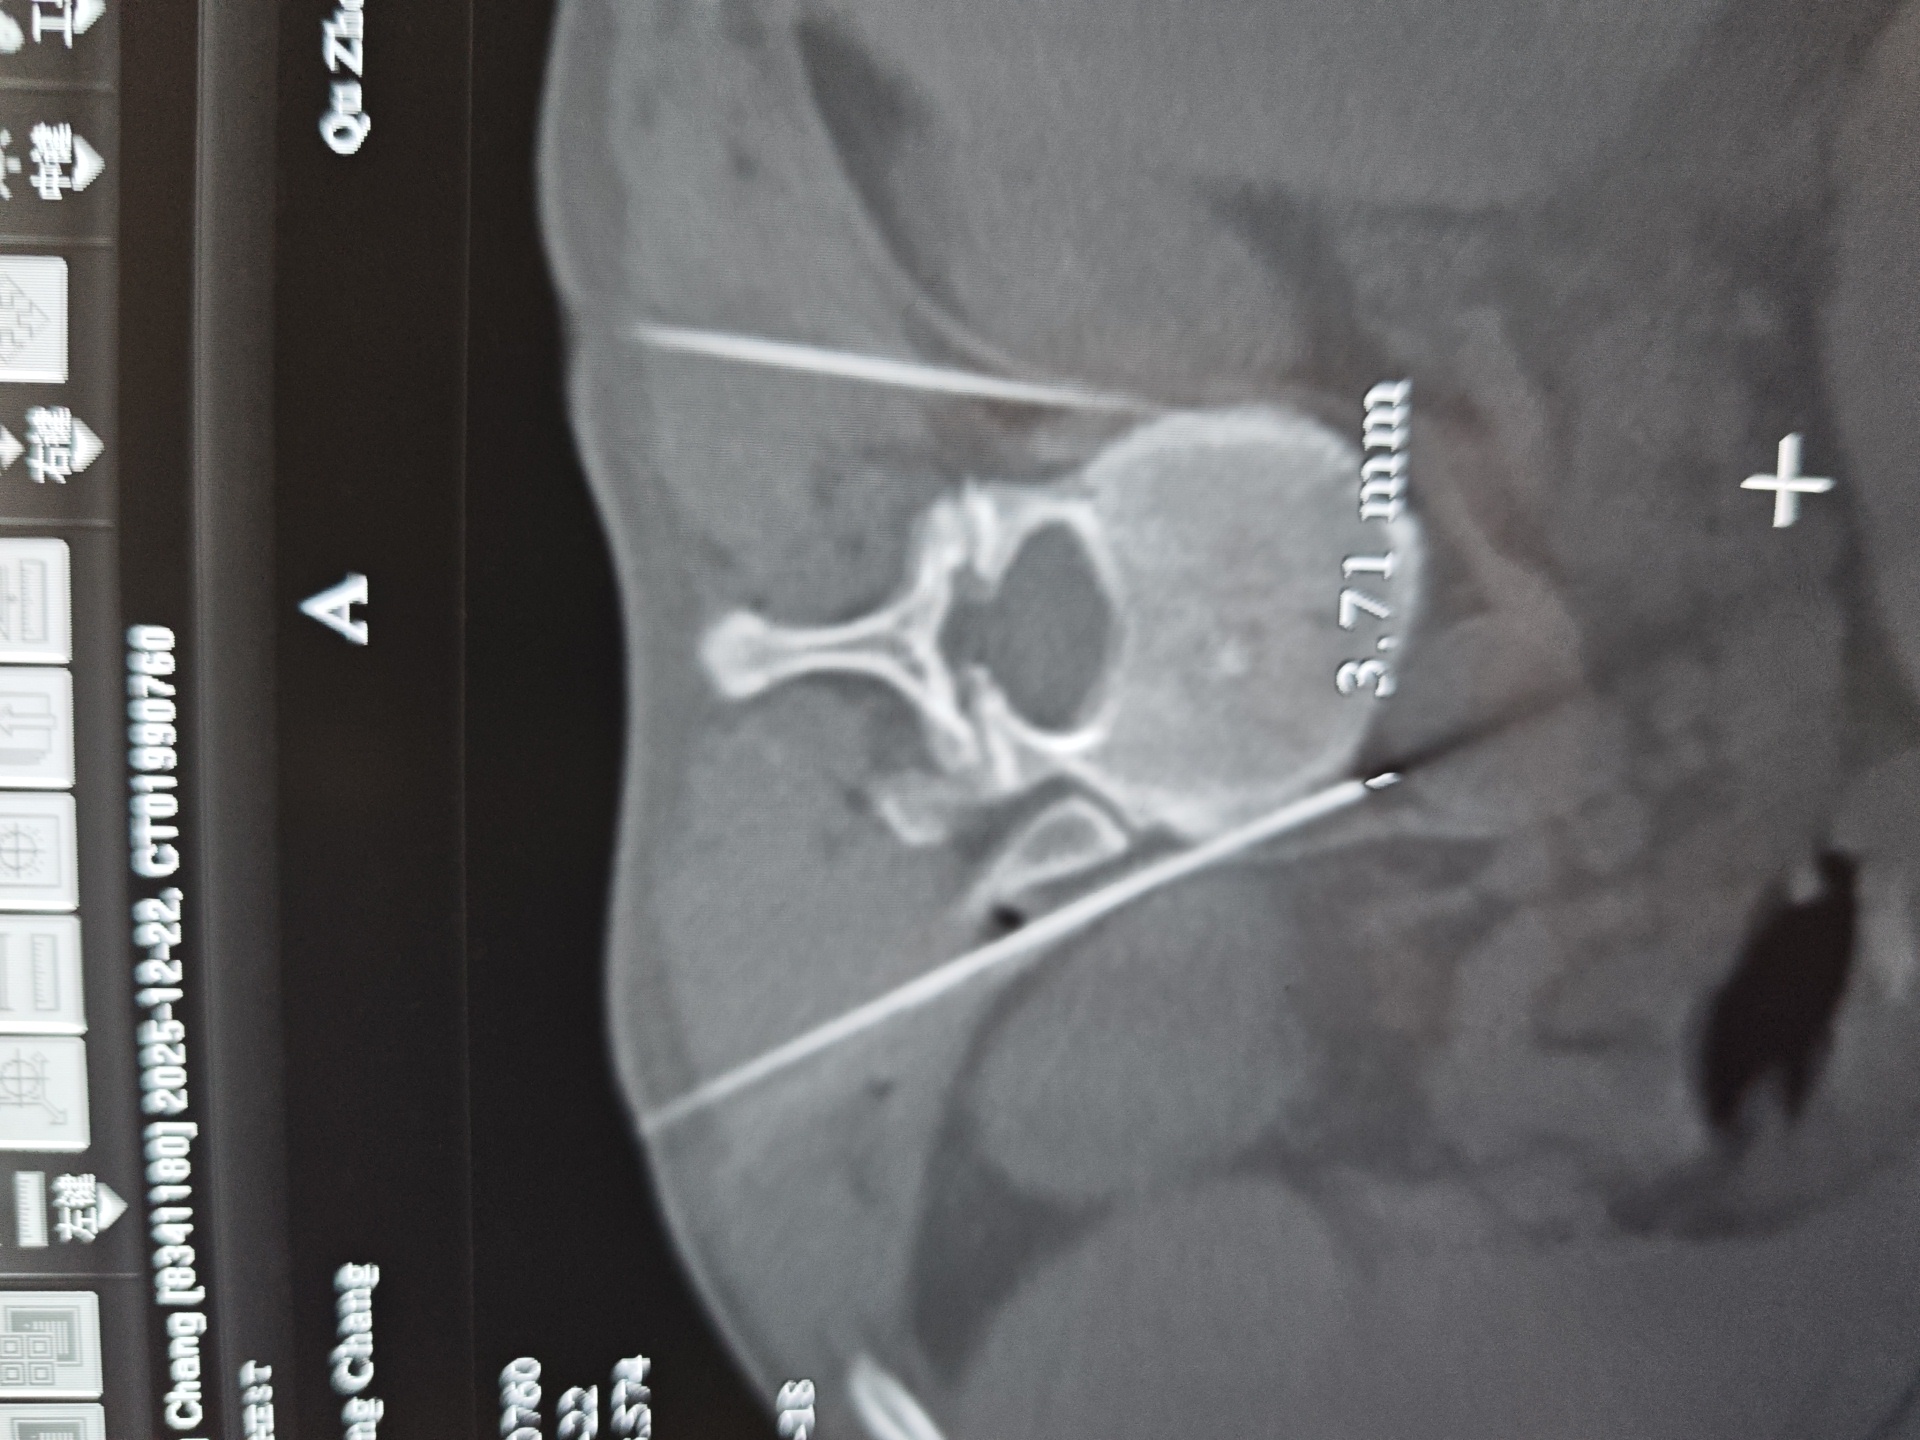

在CT引导下确定穿刺路径

局部麻醉后,将穿刺针送至目标位置

注入造影剂确认位置准确